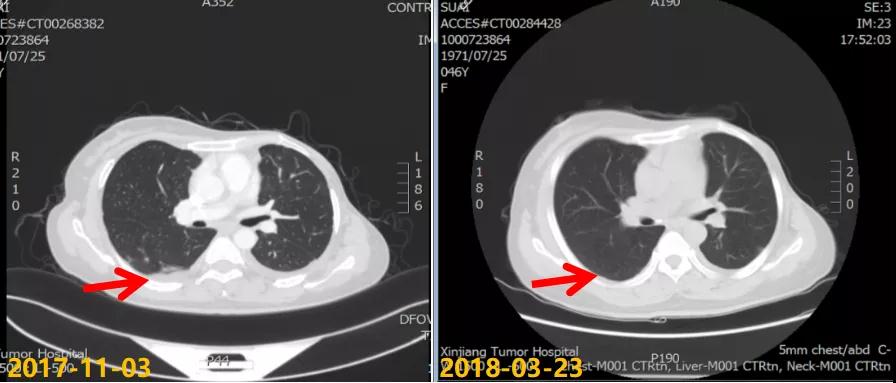

2017-11至2018-03:TX方案6周期(多西他赛120mg d1+卡培他滨1500mg po bid d1-14),化疗期间继续戈舍瑞林3.6mg ih q4w。疗效评估:前四周期略缩小但未达PR,后两周期SD,呼吸道症状明显改善。2018-04行戈舍瑞林3.6mg ih q4w联合氟维司群 500mg im q4w内分泌维持治疗,同时经MDT多学科讨论后行肝脏射频消融术。一线治疗获得36个月PFS。

本例患者为绝经前年轻女性,分子分型为luminal B型(HER2阴性)。术后FEC方案辅助化疗6周期后行戈舍瑞林联合他莫昔芬辅助内分泌治疗。患者于辅助内分泌治疗结束1年内出现双肺、胸膜和肝脏转移,经过肝脏穿刺证实分子分型仍为luminal B型(HER2阴性)。考虑患者继发性内分泌耐药(辅助内分泌治疗时间大于2年复发转移),晚期一线治疗选择TX化疗6周期,肺部、胸膜、肝脏转移灶最佳疗效评价为 SD。维持治疗调整治疗方案为氟维司群+戈舍瑞林,最佳疗效评价为 PR。该患者从一线维持治疗有36个月PFS获益。